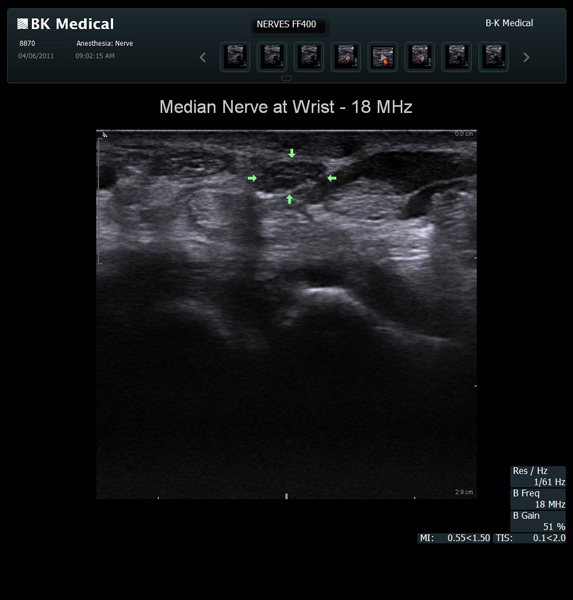

The Flex Focus 400 exp ultrasound system offers premium image quality with fast frame rates for excellent temporal resolution. The system features Automatic Mode Adjustment (AMA) to optimize high resolution B-Mode Imaging when changing modes and depth.

Transducers Designed for Guidance

BK Medical offers high-frequency linear transducers, imaging from 18-2 MHz for upper and lower extremities, and curved array abdominal transducer 8820e for special deep nerves or paravertebral/spinal applications. Our transducers provide superb detail that makes it easy to see your needle during procedures.